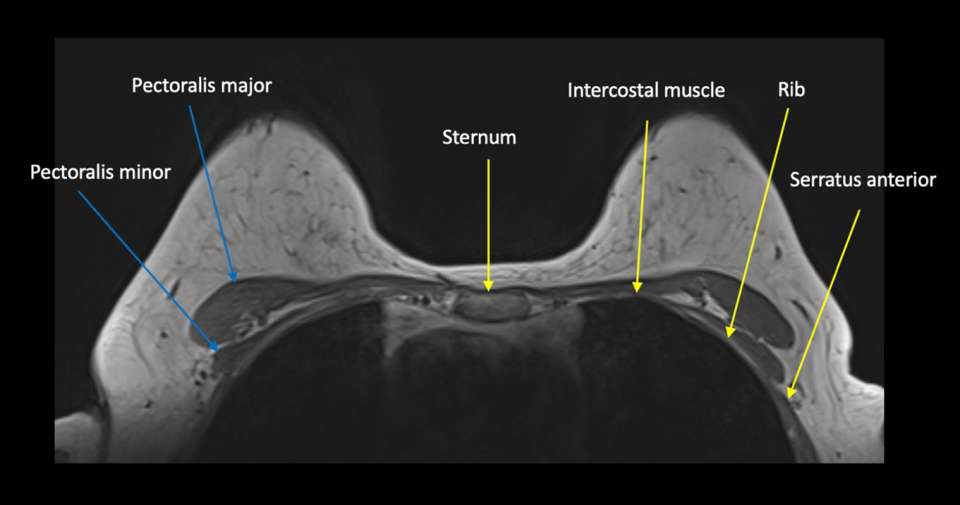

Case 2: Patient with history of right breast cancer status post right mastectomy presenting with skin erythema. Patient underwent diagnostic MRI which demonstrated the following (Figure 3).

Case: Chest Wall Invasion Figure 3

Figure 3: Bilateral breast MRI T1 post-contrast image demonstrates an irregular enhancing mass in the midline at the cleavage with abnormal enhancement involving the sternum (red circle) and extending to the intercostal space of the chest wall (green arrow).

The patient was diagnosed with invasive ductal carcinoma and treated with neoadjuvant chemotherapy.